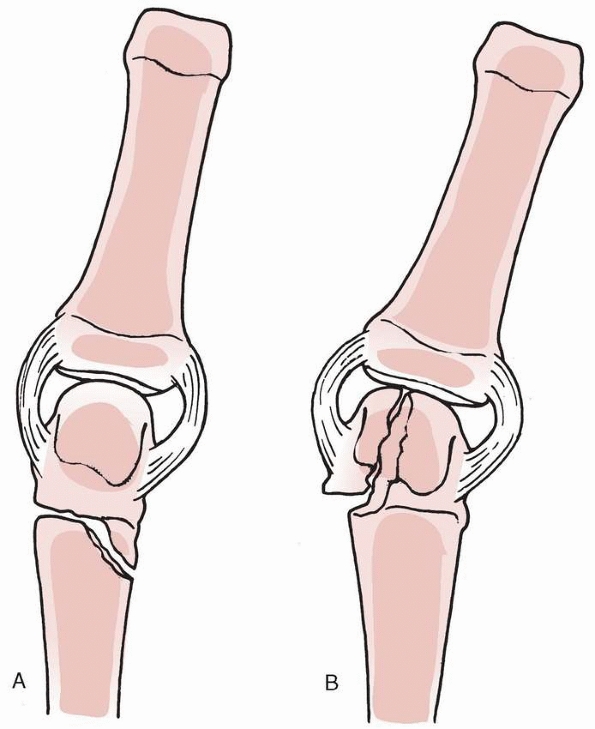

![]() |

FIGURE 8-24 A,B.

Postoperative photographs of the patient shown in Figure 8-25 after the antenna procedure. The procedure involved a volar V-Y advancement flap to cover the distal tip, elevation of the sterile matrix, and the nail supported using three Kirschner-wires. C. Line drawings demonstrating technique of elevation and support of the sterile matrix with wires. (A,B. Courtesy of William B. Kleinman, MD. C. Reprinted from Atasoy E, Godfrey A, Kalisman M. The “antenna” procedure for the “hook-nail” deformity. J Hand Surg [Am] 1983;8:55, with permission.) |